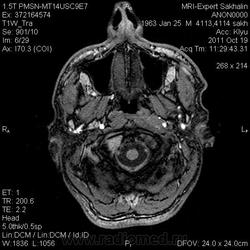

объемное образование ската с распространением на пирвмидку височной кости, область атланто-окципитального сочленения, не выраженно контрастируется- может хордома?-хотя сиггнал по Т2 для нее не типичен ( более характерен гиперинтенсивный МРС) Но ведь возможны вариации?. А КТ не делали?.

Ирина, спасибо!КТ делали- в выписке "образование крылонебной ямки", даже без описания и снимков!